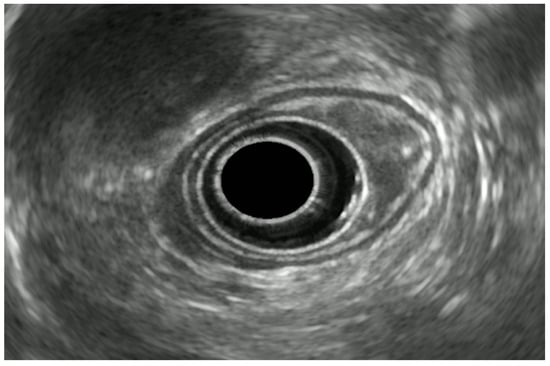

5.1. Esophagus

5.1.1. Esophageal Cancer

5.1.2. EUS in Superficial Esophageal Cancer

5.1.3. EUS in Advanced Esophageal Cancer